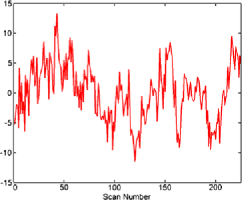

The subject in Figure 3 seems to exhibit strong deviations from stationarity—in fact, the -value associated with this subject is below based on the bootstrap test given in Section 7. It should be stressed that the change detection is a global hypothesis test combined over all components considered. In this way, while taking more components will help increase the chance that the change is present in one, it will come at the cost of the size of the change needed in finite samples for an omnibus test of this type. However, the subject shown in the figure did cause a rejection of the null hypothesis of no change both in the 64 and 125 subspace size omnibus tests. While the pictures in Figure 3 indicate that an epidemic change is indeed a good first approximation for the nonstationarities occurring for this particular subject, more deviation (maybe more change-points) does seem to be present. In Figure 4, a second subject is shown with a much smaller deviation from stationarity (most of the components seem to have little to no possible mean change present), which is significant but does not survive the false discovery rate (FDR) correction (see Section 4.3).

When testing subject 48501 from the connectome data, from whom the components can be seen in Figure 4, an epidemic change seems to be quite a good model for several components, but only a small part of the time series deviates from stationarity. For example, component 7 in Figure 6 shows a less pronounced but still plausible epidemic change compared with component 23 of subject 01018 in Figure 5. However, as can be seen in another component (Figure 7) from subject 48501, some of the components seem to be stationary without any change present.

Given that nearly 200 subjects were tested, a multiple comparison correction was implemented using the independent FDR method by Benjamini and Hochberg (1995). The use of an independent FDR is based on the fact that the comparisons are being taken across subjects who can be assumed to be independent of each other. Subject 01018 (Figure 3) survived the FDR correction and evidence was still found of nonstationarities being present. Subject 48501, whose projections are seen in Figure 4, also rejected the null hypothesis but only at about a 3% level, hence not surviving the FDR correction.

Finally, in Figure 2 the subject shown has components which do not indicate level shifts and, in fact, the null hypothesis is not rejected for this subject, either with or without FDR correction.